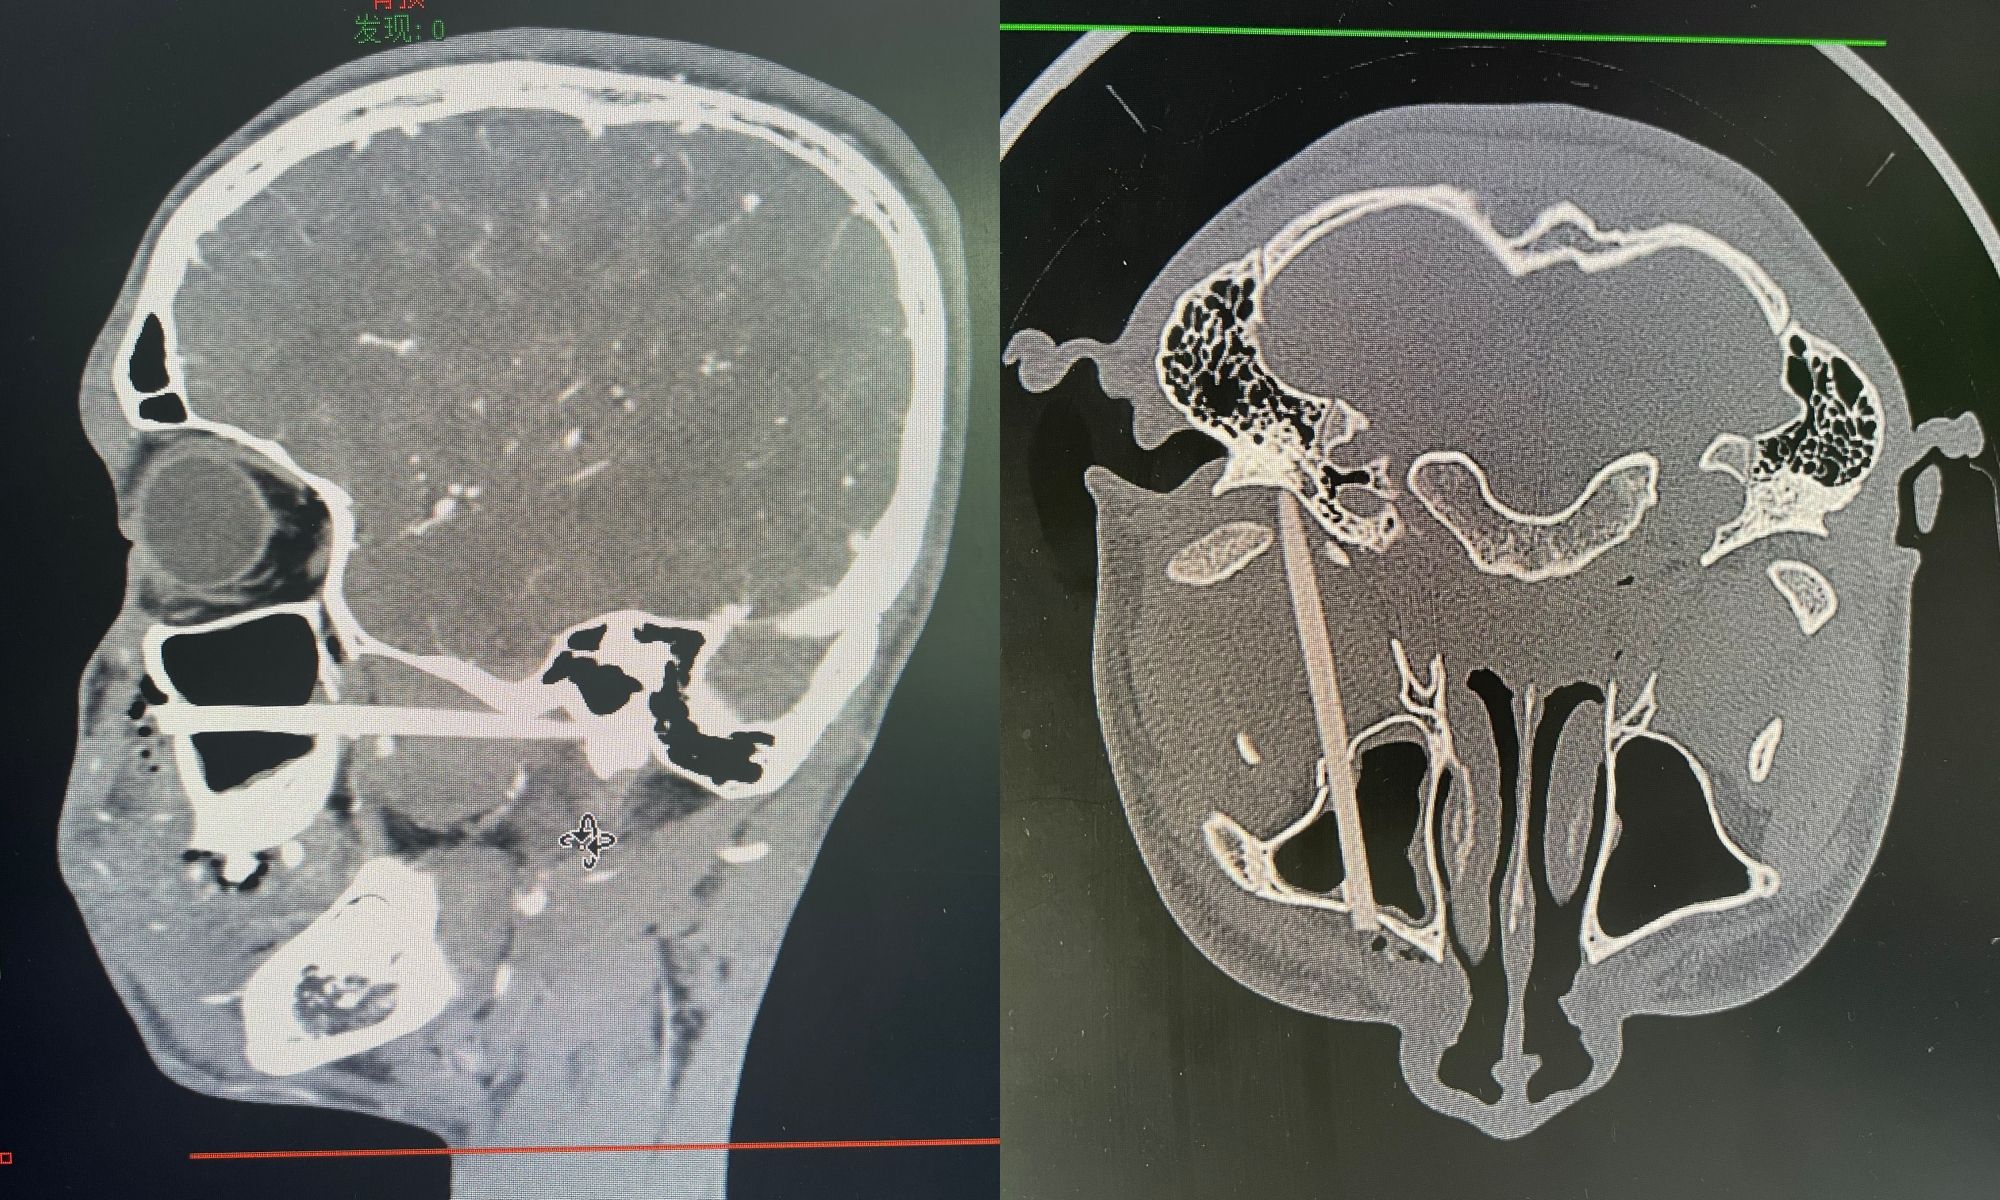

小捷抵达医院后,唇腭裂外科值班医生张宗敏迅速接诊并收治入院,科室主任任战平团队高度重视,第一时间安排患者进行增强CT检查。检查结果显示,筷子自左侧鼻腔插入,不仅穿通了上颌窦前方和外侧骨壁,更是进入颞下颌关节窝,且紧贴上颌动脉分支。筷子的位置和走向极为复杂,任何操作都可能引发血管破裂大出血等严重后果,救治难度极大。

面对如此棘手的情况,任战平主任立即组织了术前讨论。由于留在鼻腔外的筷子被患者拔断,断端位置较深,而鼻腔的伤口过小,导致无法经鼻腔的伤口看到筷子断端,也无法通过鼻腔取出,因此设计了口内切口入路,既能确保术野,也能避免扩大鼻腔切口造成的瘢痕。团队成员围绕增强CT 影像,分析异物与血管和周围组织的关系,细致评估术中取出时可能出现的出血等风险,制定了周全的手术方案。

术中发现异物插入颌骨内阻力大,直接贸然取出可能发生断裂,陶永炜副主任凭借精湛的医术和丰富的经验,张宗敏医生紧密配合,用超声骨刀微创解除异物周围骨阻力并充分保护眶下神经,小心谨慎操作,成功将异物顺利取出,取出的异物长达8厘米,术中同期清理左侧上颌窦内积血并完成了上颌窦修补术。手术过程中未发生重要血管破裂大出血,出血量控制良好,患者目前生命体征平稳,正在接受进一步观察与治疗。